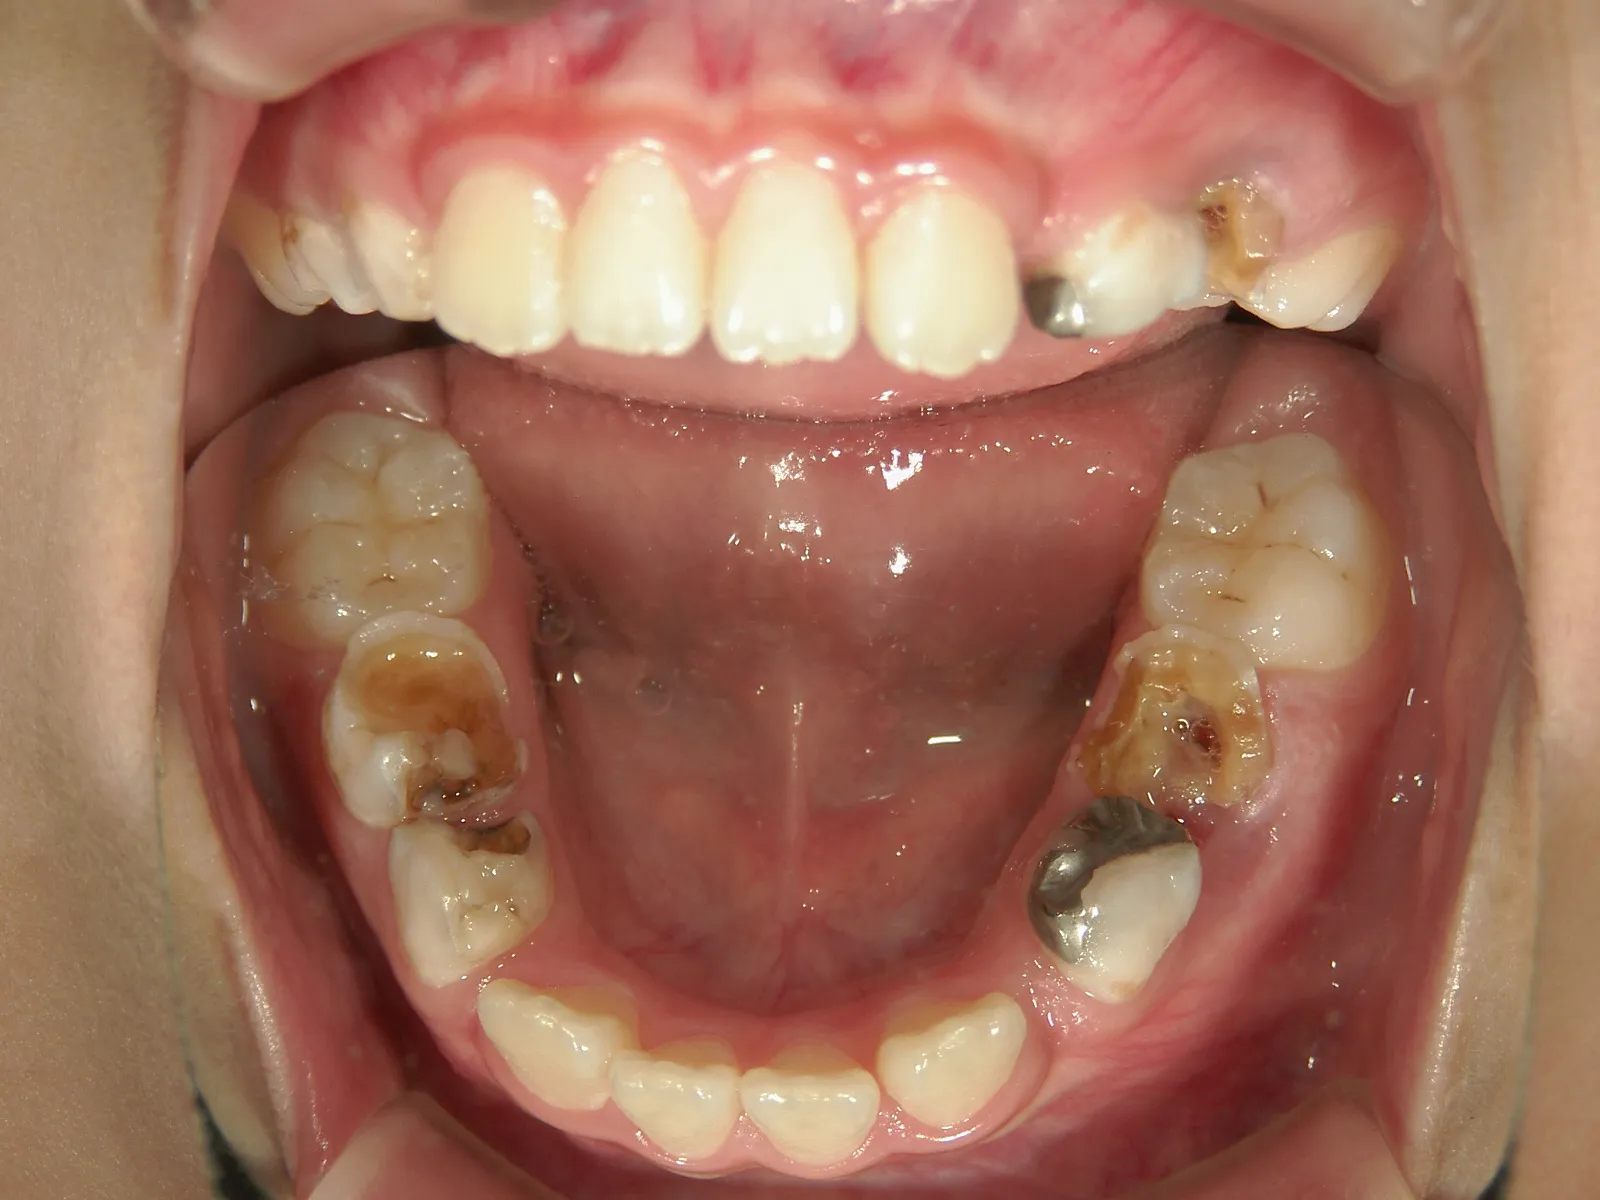

④連続抜歯

明らかに抜歯をしないと歯がちゃんと並ばないぐらい顎が小さいケースでは、乳歯のC,Dと永久歯の4番を抜歯してしまう方法です。この方法は奥歯の噛み合わせが良いケースに限られるため、適応ケースはあまり多くありません。

犬歯(3番目の歯)が生えてくるスペースがありません

連続抜去後